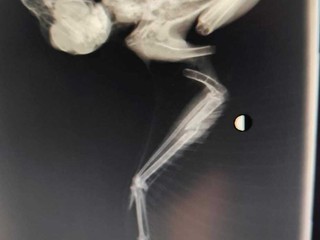

"Qualche mese fa ci hanno segnalato una poiana a terra, sofferente, incapace di volare. L’abbiamo prontamente recuperata e portata dal veterinario e le radiografie hanno mostrato diversi pallini: uno vicino al cuore, uno vicino al rene, entrambi inoperabili - spiegano dall'ente - Ora l’animale mostra evidenti sintomi di saturnismo, causato dal piombo: una lenta agonia che non dovrebbe esistere".

"Pochi giorni fa ci è stato segnalato un biancone dalle parti di Ventimiglia, a terra e sofferente. Anche lui, dopo le radiografie, è risultato pieno di pallini in tutto il corpo e con un’ala fratturata. È tuttora monitorato costantemente con la speranza di salvarlo - continuano - Oggi (ieri.ndr) abbiamo rinvenuto ad Alpicella, in provincia di Savona, un allocco in gravissime condizioni. Nello studio veterinario, durante le radiografie abbiamo chiaramente visto numerosi pallini che gli hanno fratturato ali e zampe, arrivando perfino a colpire gli organi interni. La veterinaria non ha potuto fare altro che constatarne il decesso".